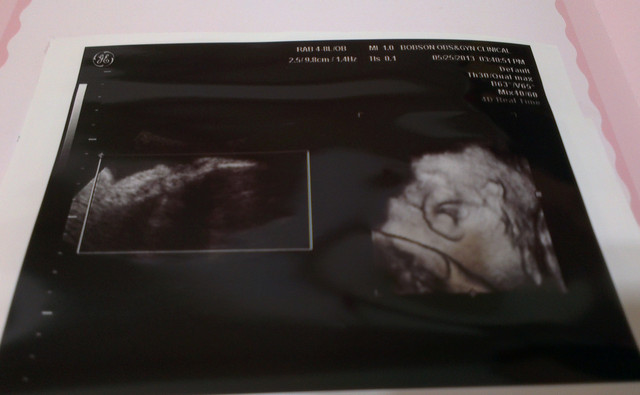

還是最後笑起來的比較可愛

醫生說章魚妹已經足月

所以隨時要生都可以

不用擔心早產的問題

章魚妹

頭圍:

8.58 cm

肚圍:

32.44 cm

加起來重量為

2826g